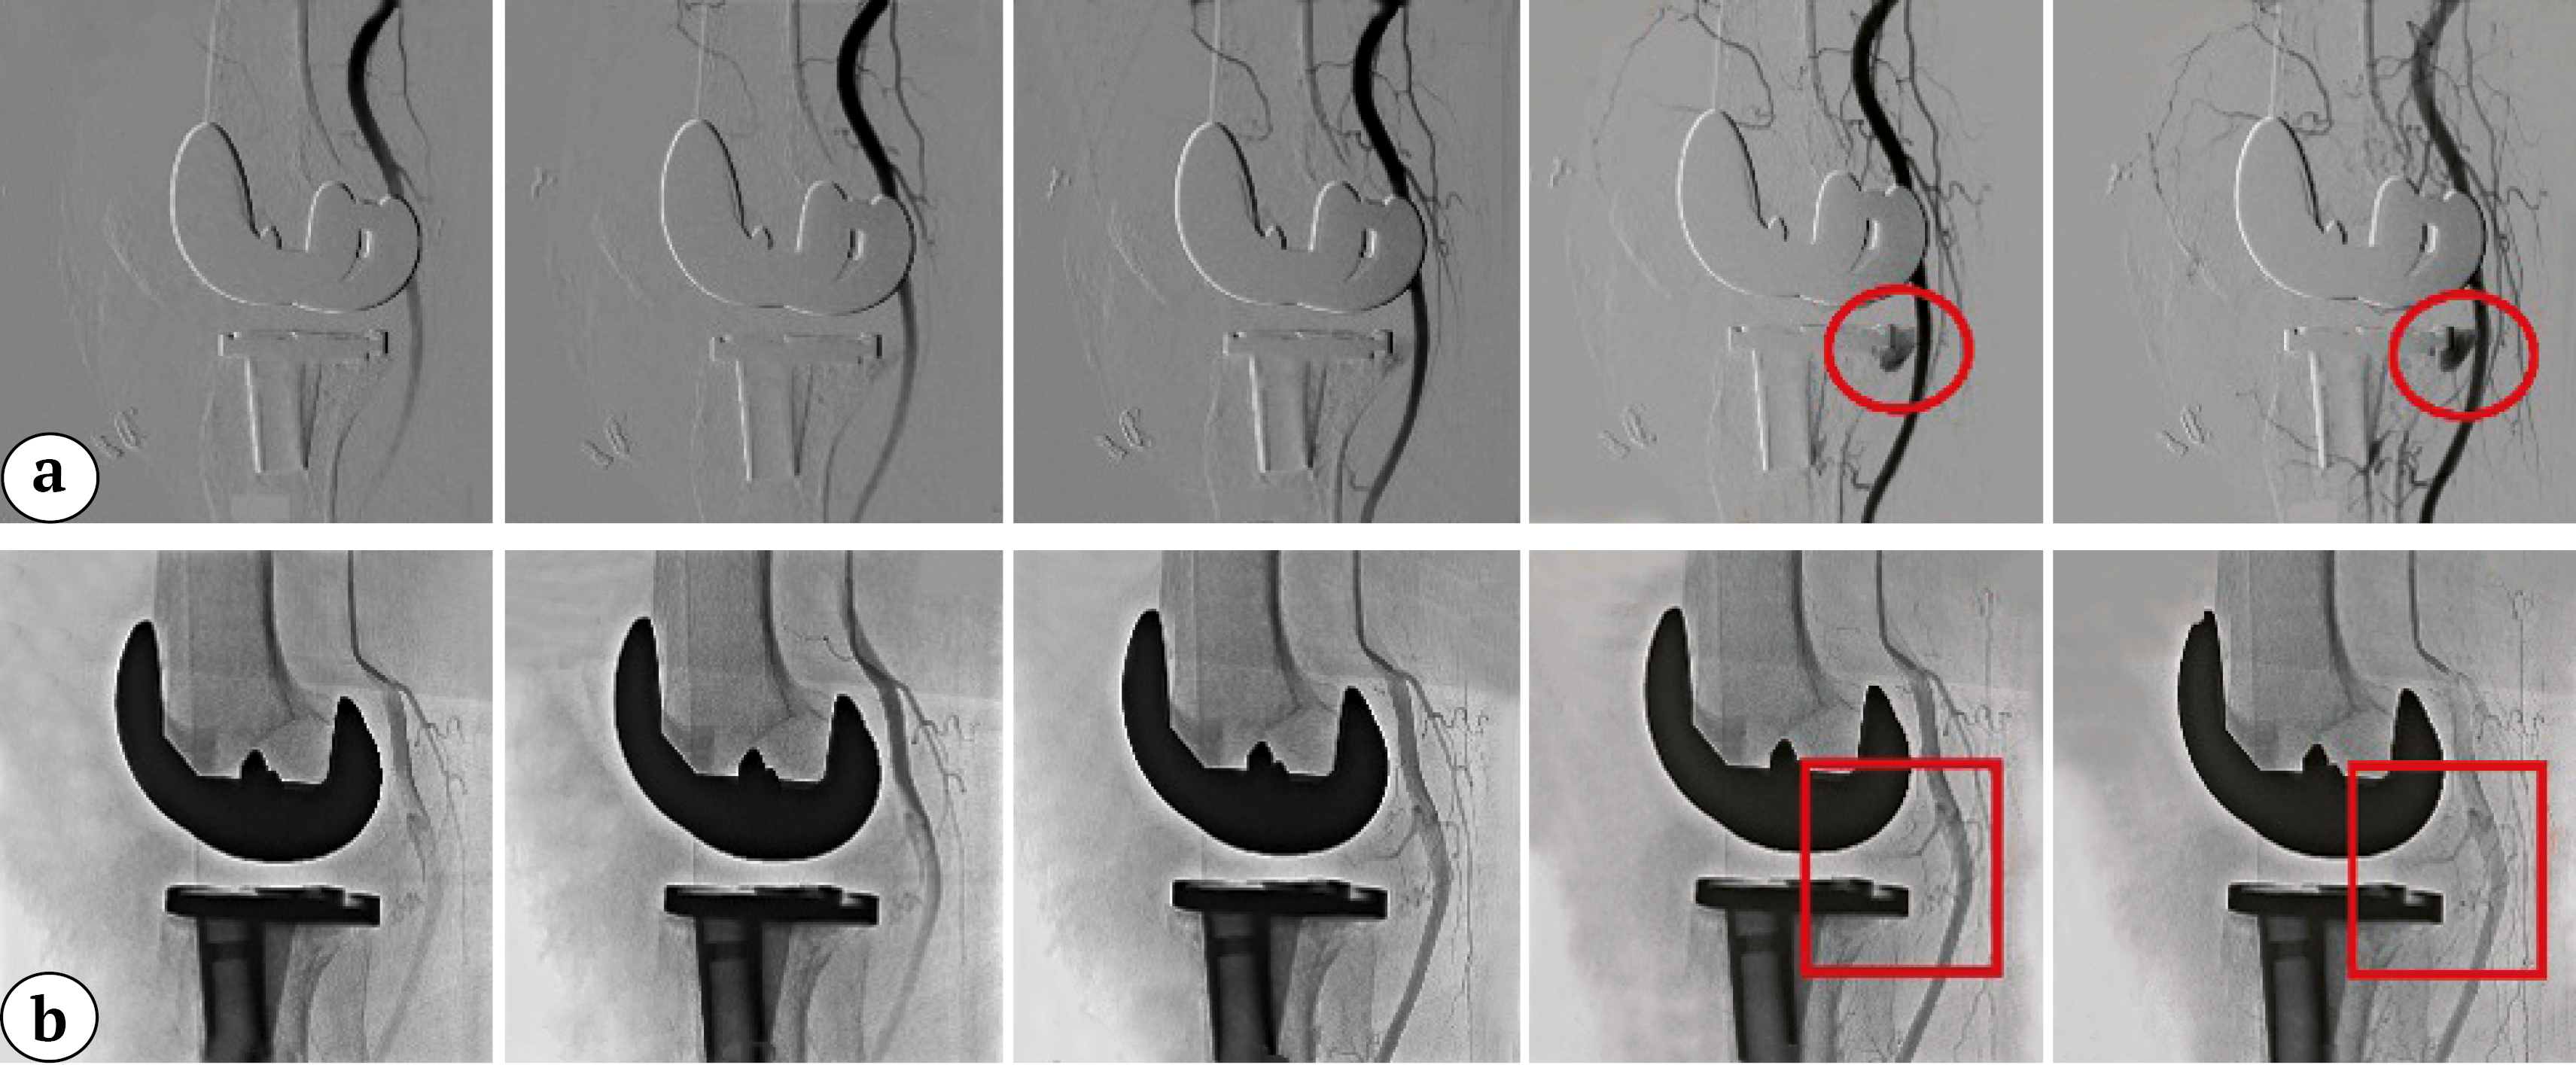

After consultation, an intervention radiologist advised an immediate CT angiography with contrast. It revealed a contrast-filled lesion near the anteromedial border of the tibial insert, diagnosed as pseudoaneurysm originating from the IMGA and treated at the same session by endovascular coil embolization (Figure 1).

Figure 1. CT angiography with contrast delineates a pseudoaneurysm of the inferior medial genicular artery: a — pre-embolization CT angiography images showing the knee prosthesis and leakage of the contrast material near the border of the tibial insert (red circle); b — post-embolization CT angiography images showing sealing and obliteration of the pseudoaneurysm after coil embolization with no leakage of the contrast material (red squares)